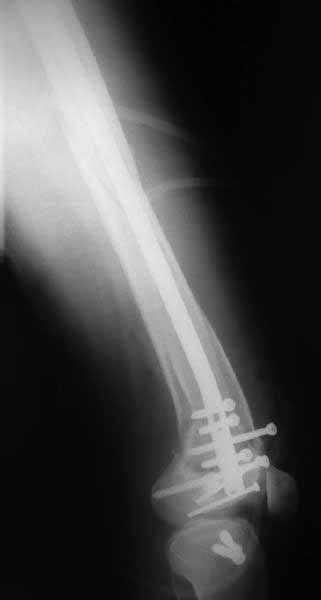

Ответ на эту часть Вашего поста – вложенный файл. Больная оперирована неделю назад по поводу открытого перелома дистального эпиметафиза бедренной кости. После операции она идёт в рентгенкабинет для выполнения послеоперационной контрольной рентгенографии, представленной на слайдах 10 и 11. Узнав, почему её фотографируют, просила передать Вам, Антон, привет.

наружный мыщелок не дорепонироавн - это приводит к вальгусной деформации оси коленного сустава, очень критично для последующей функции.